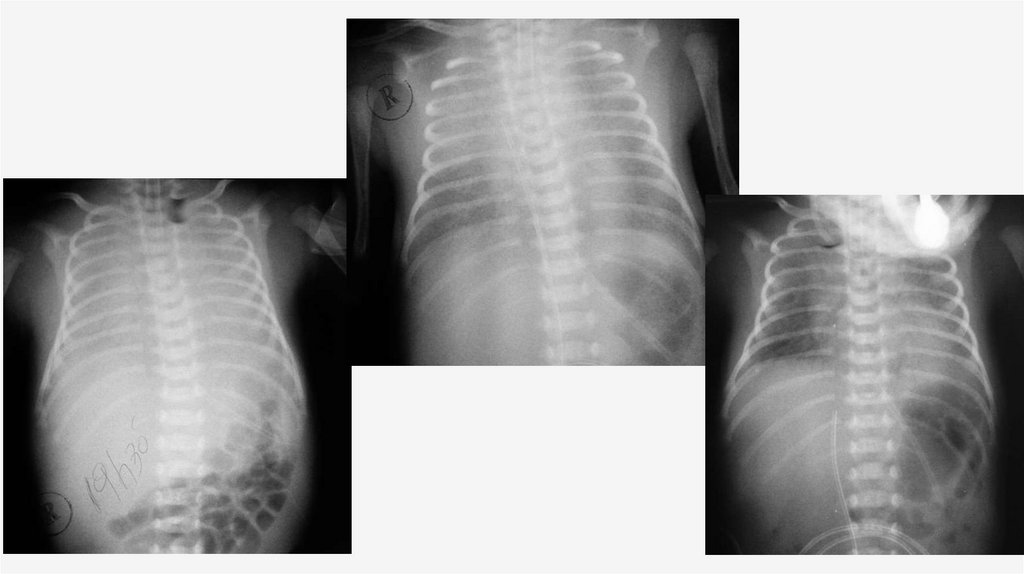

РЕНТГЕНОЛОГИЧЕСКОЕ

ИССЛЕДОВАНИЕ

• При рентгенологическом исследовании органов грудной клетки отмечается

характерная триада признаков: диффузное снижение прозрачности легочных

полей, границы сердца не дифференцируются, «воздушная» бронхограмма.

• В качестве осложнений РДС возможно развитие синдромов утечки воздуха из

легких, таких как пневмоторакс, пневмомедиастинум, пневмоперикард и

интерстициальная эмфизема легких.